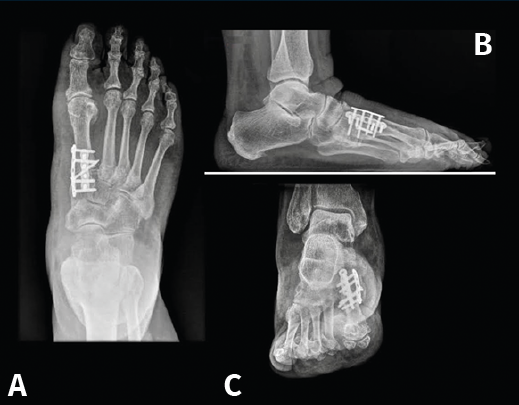

Figura 14. Caso del Dr. Martín Ferreyra. Imágenes radiológicas postoperatorias. A: dorsoplantar; B: perfil; C: axial de los sesamoideos. Obsérvese la corrección obtenida y la ubicación de los sesamoideos antes y después de la cirugía.

Es por ello que en la actualidad autores como E. y P. Wagner(68) realizan una osteotomía tridimensional, no solo en el plano transversal, a la que denominan PROMO. En el caso de la artrodesis cuneometatarsiana sucede lo mismo y una de las tendencias actuales es realizar un Lapidus modificado tridimensional(69,70), como puede verse en el caso de M. Ferreyra (Figuras 13 a 15), en el que la estabilización con 2 placas permite una carga precoz.